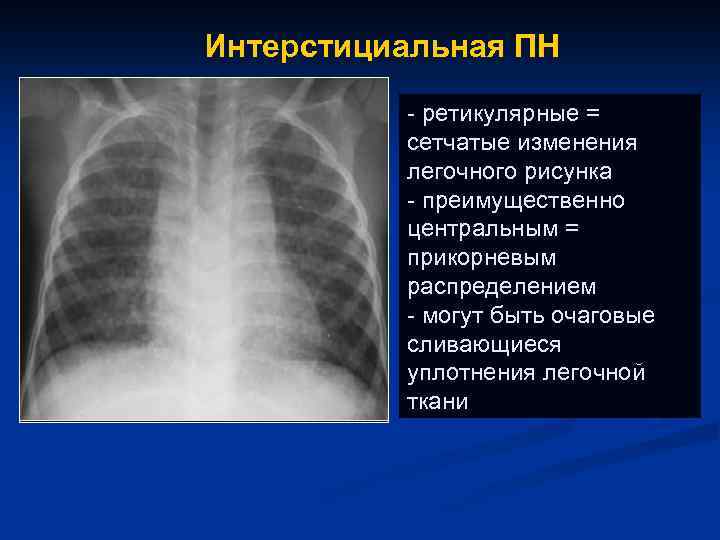

Интерстициальная ПН - ретикулярные = сетчатые изменения легочного рисунка - преимущественно центральным = прикорневым распределением - могут быть очаговые сливающиеся уплотнения легочной ткани